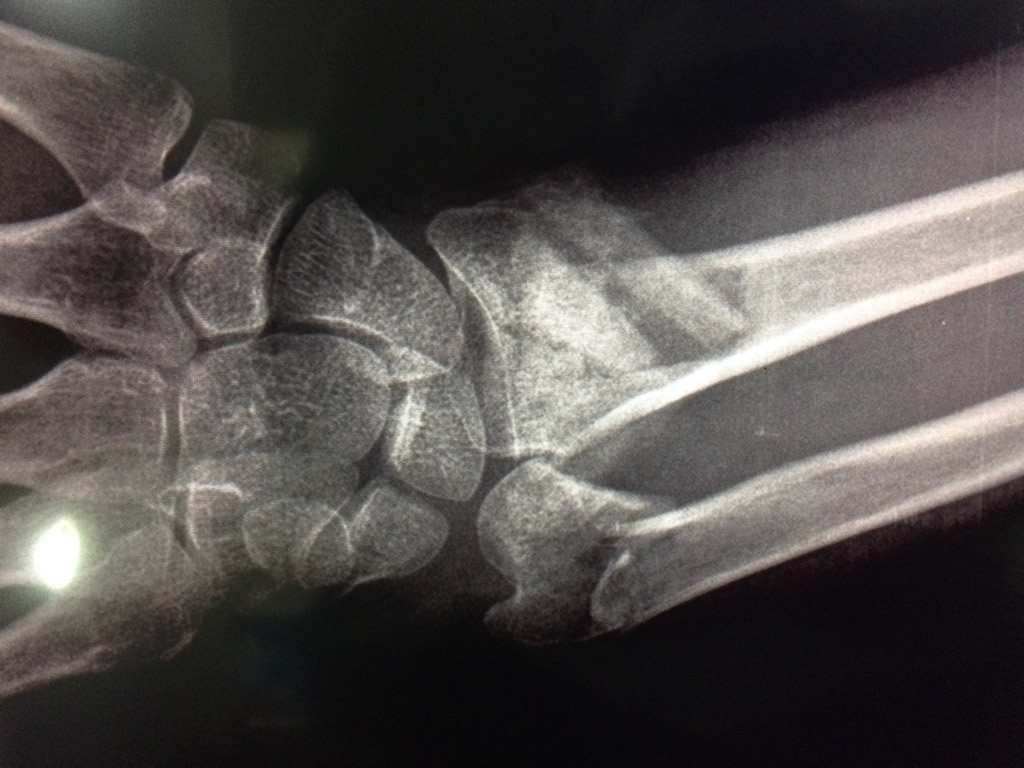

Calcaneo - Cirugías de Muñecas y Manos

Los procedimientos más comunes en cirugía de la mano son aquellos destinados a reparar traumatismos, incluyendo lesiones de tendones, nervios, vasos sanguíneos, y articulaciones; huesos fracturados; y quemaduras, cortes, y otros daños de la piel.